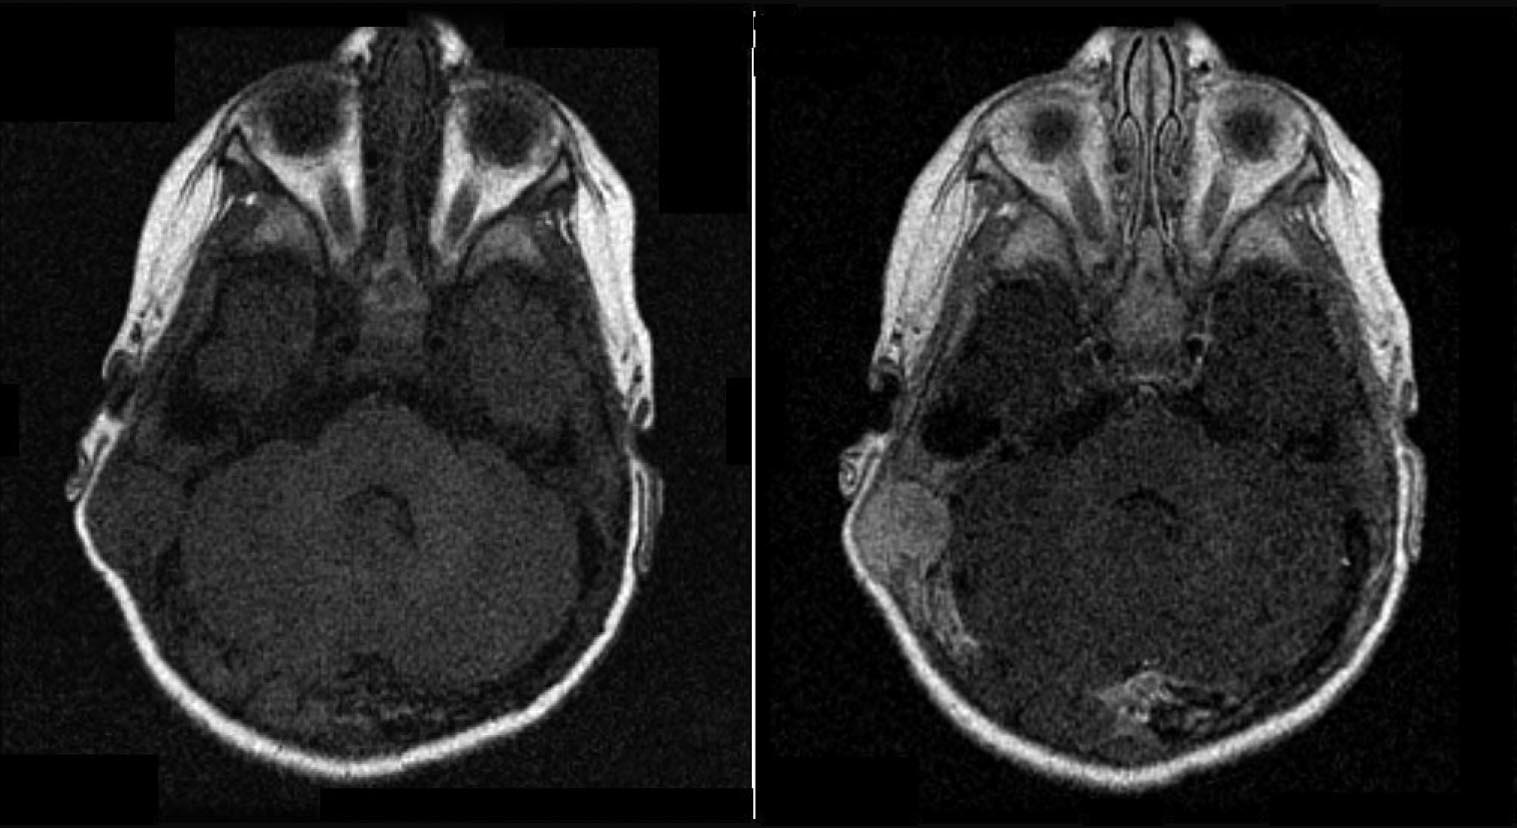

A questo punto viene eseguita una Risonanza Magnetica Nucleare (RMN) per definire l'eventuale coinvolgimento dell'encefalo: si documenta una lesione che determina un'ampia osteolisi a tutto spessore della teca cranica, giungendo a contatto con il cervelletto (Figura 1 e Figura 2). La Tomografia Computerizzata (TC) conferma il reperto (Figura 3).

Figura 1. Immagini alla RMN assiali dipendenti dal T1, senza e con mdc.